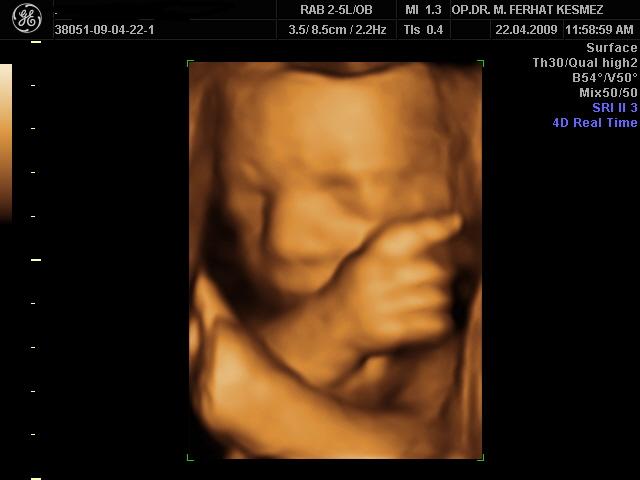

4 Boyutlu Ultrason